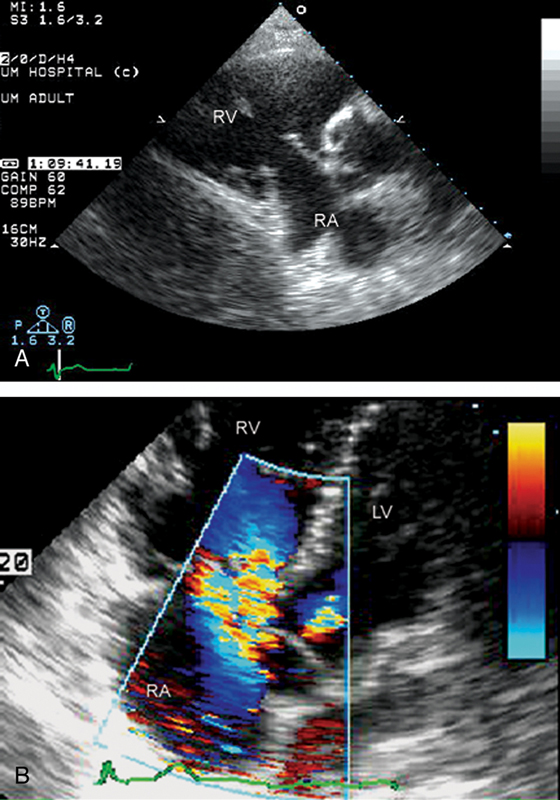

فحوصات تشخيصية لبعض امراض القلب والشرايين التاجية